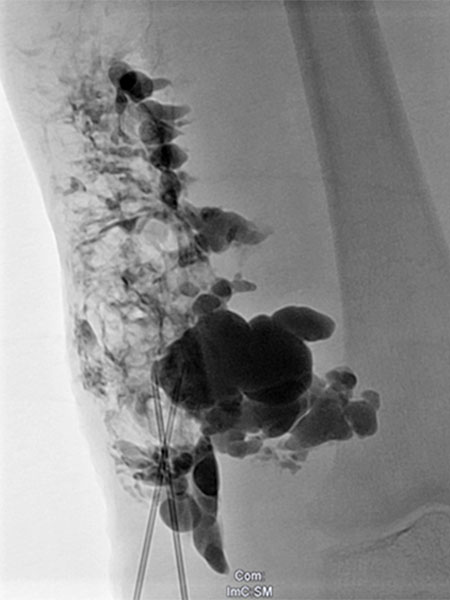

Lymphography with contrast injection directly into the lymphatic malformation subcutaneously, underneath the capillary malformation laterally on the thigh which is visible on the skin. The entire lymphatic malformation is contrasted from this needle position. Thus the ideal position for sclerosing this portion.

Re-puncture and lymphography with contrast injection will contrast additional parts of the lymphatic malformation, which can then be sclerosed.

Injection of sclerosant (in this case picibanil = OK-432), which is in itself non-contrasting, displaces the previously injected contrast. In this way, the entire lymphatic malformation is sclerosed in successive steps. This results in sealing of the skin and decreases future lymphorrhea. The marginal vein is additionally occluded by radiofrequency ablation (not shown) to prevent thromboembolism.